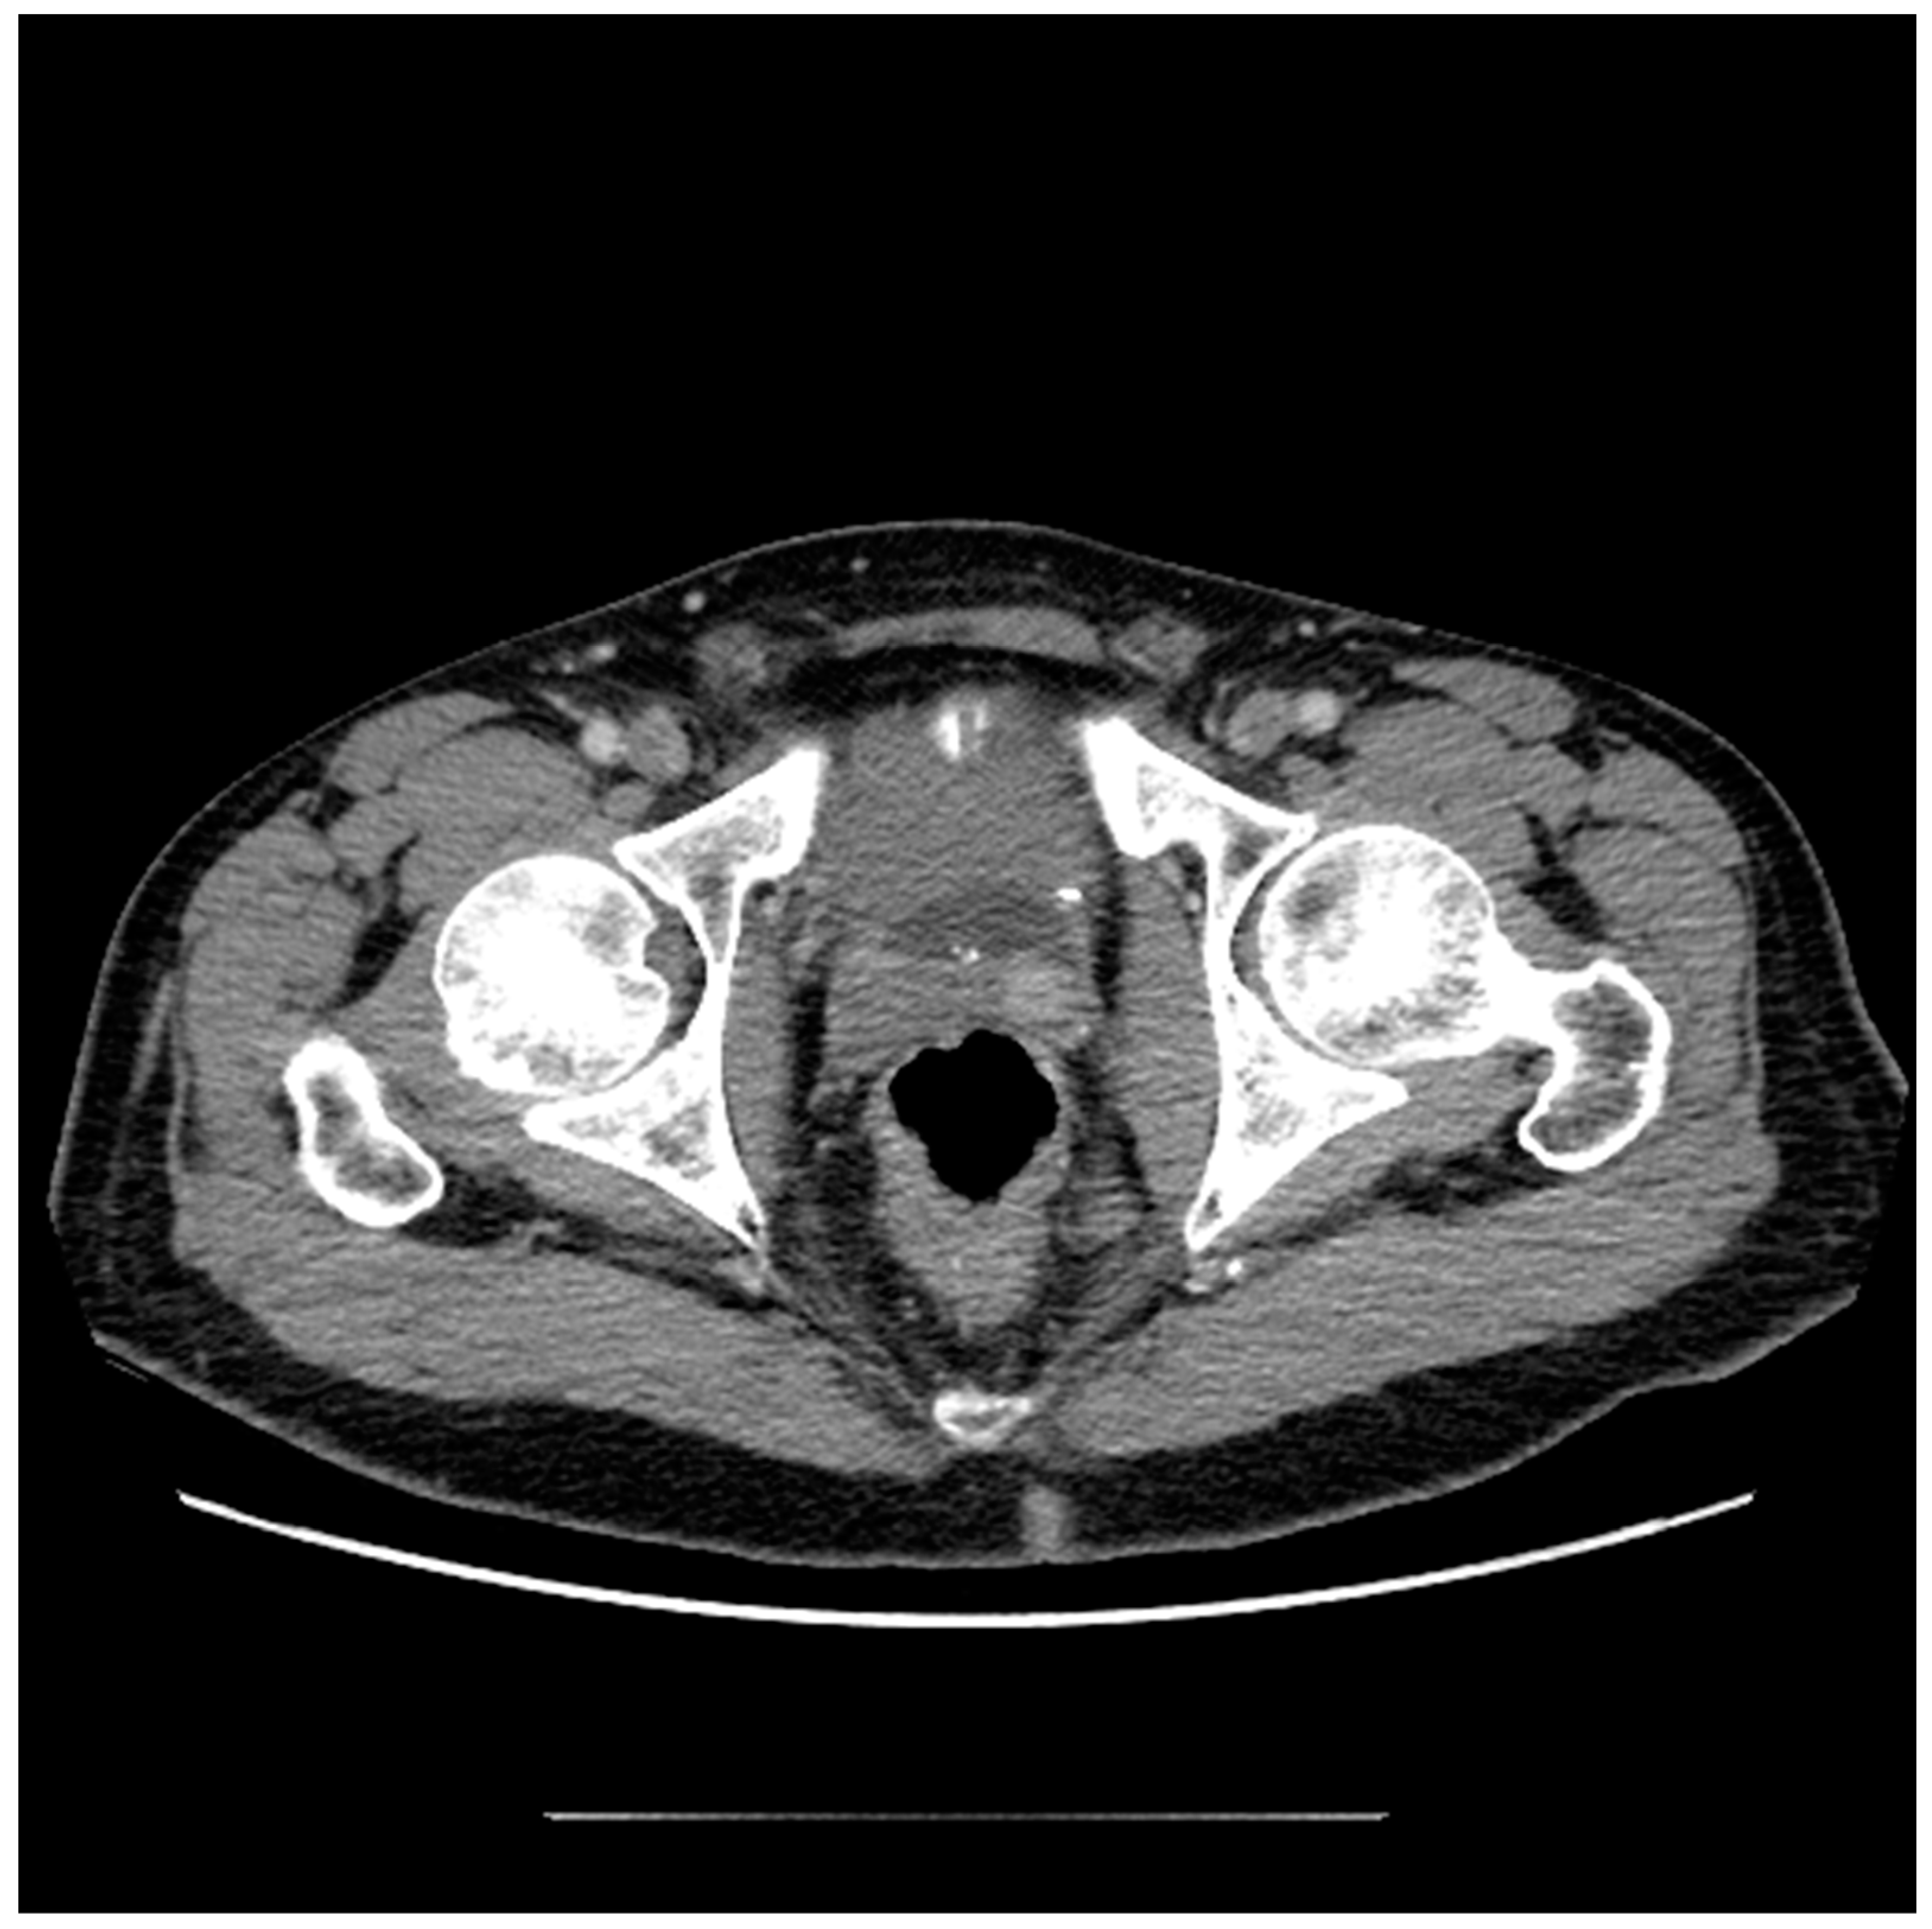

Figure 7. Coronal CT appearance of UroLift device indicated by linear densities within the bilateral prostate gland.

The prostatic urethral lift (PUL), commonly referred to as UroLift, is a clip delivery system that involves the placement of clips under cystoscopic vision that retracts obstructing prostatic tissue. Importantly, the AUA guidelines suggest candidates for this method should not have an obstructive middle lobe, which is easily identifiable in most imaging modalities. The advantages of PUL include the ability to perform in an office without the use of general anesthesia, as well as the preservation of tissue, which provides patients with a higher likelihood of preserving erectile and ejaculatory function [72]. Upon imaging, PUL has an appearance similar to brachytherapy seeds, but there will not be as many present, and they will be confined to the central prostate (Figure 7).